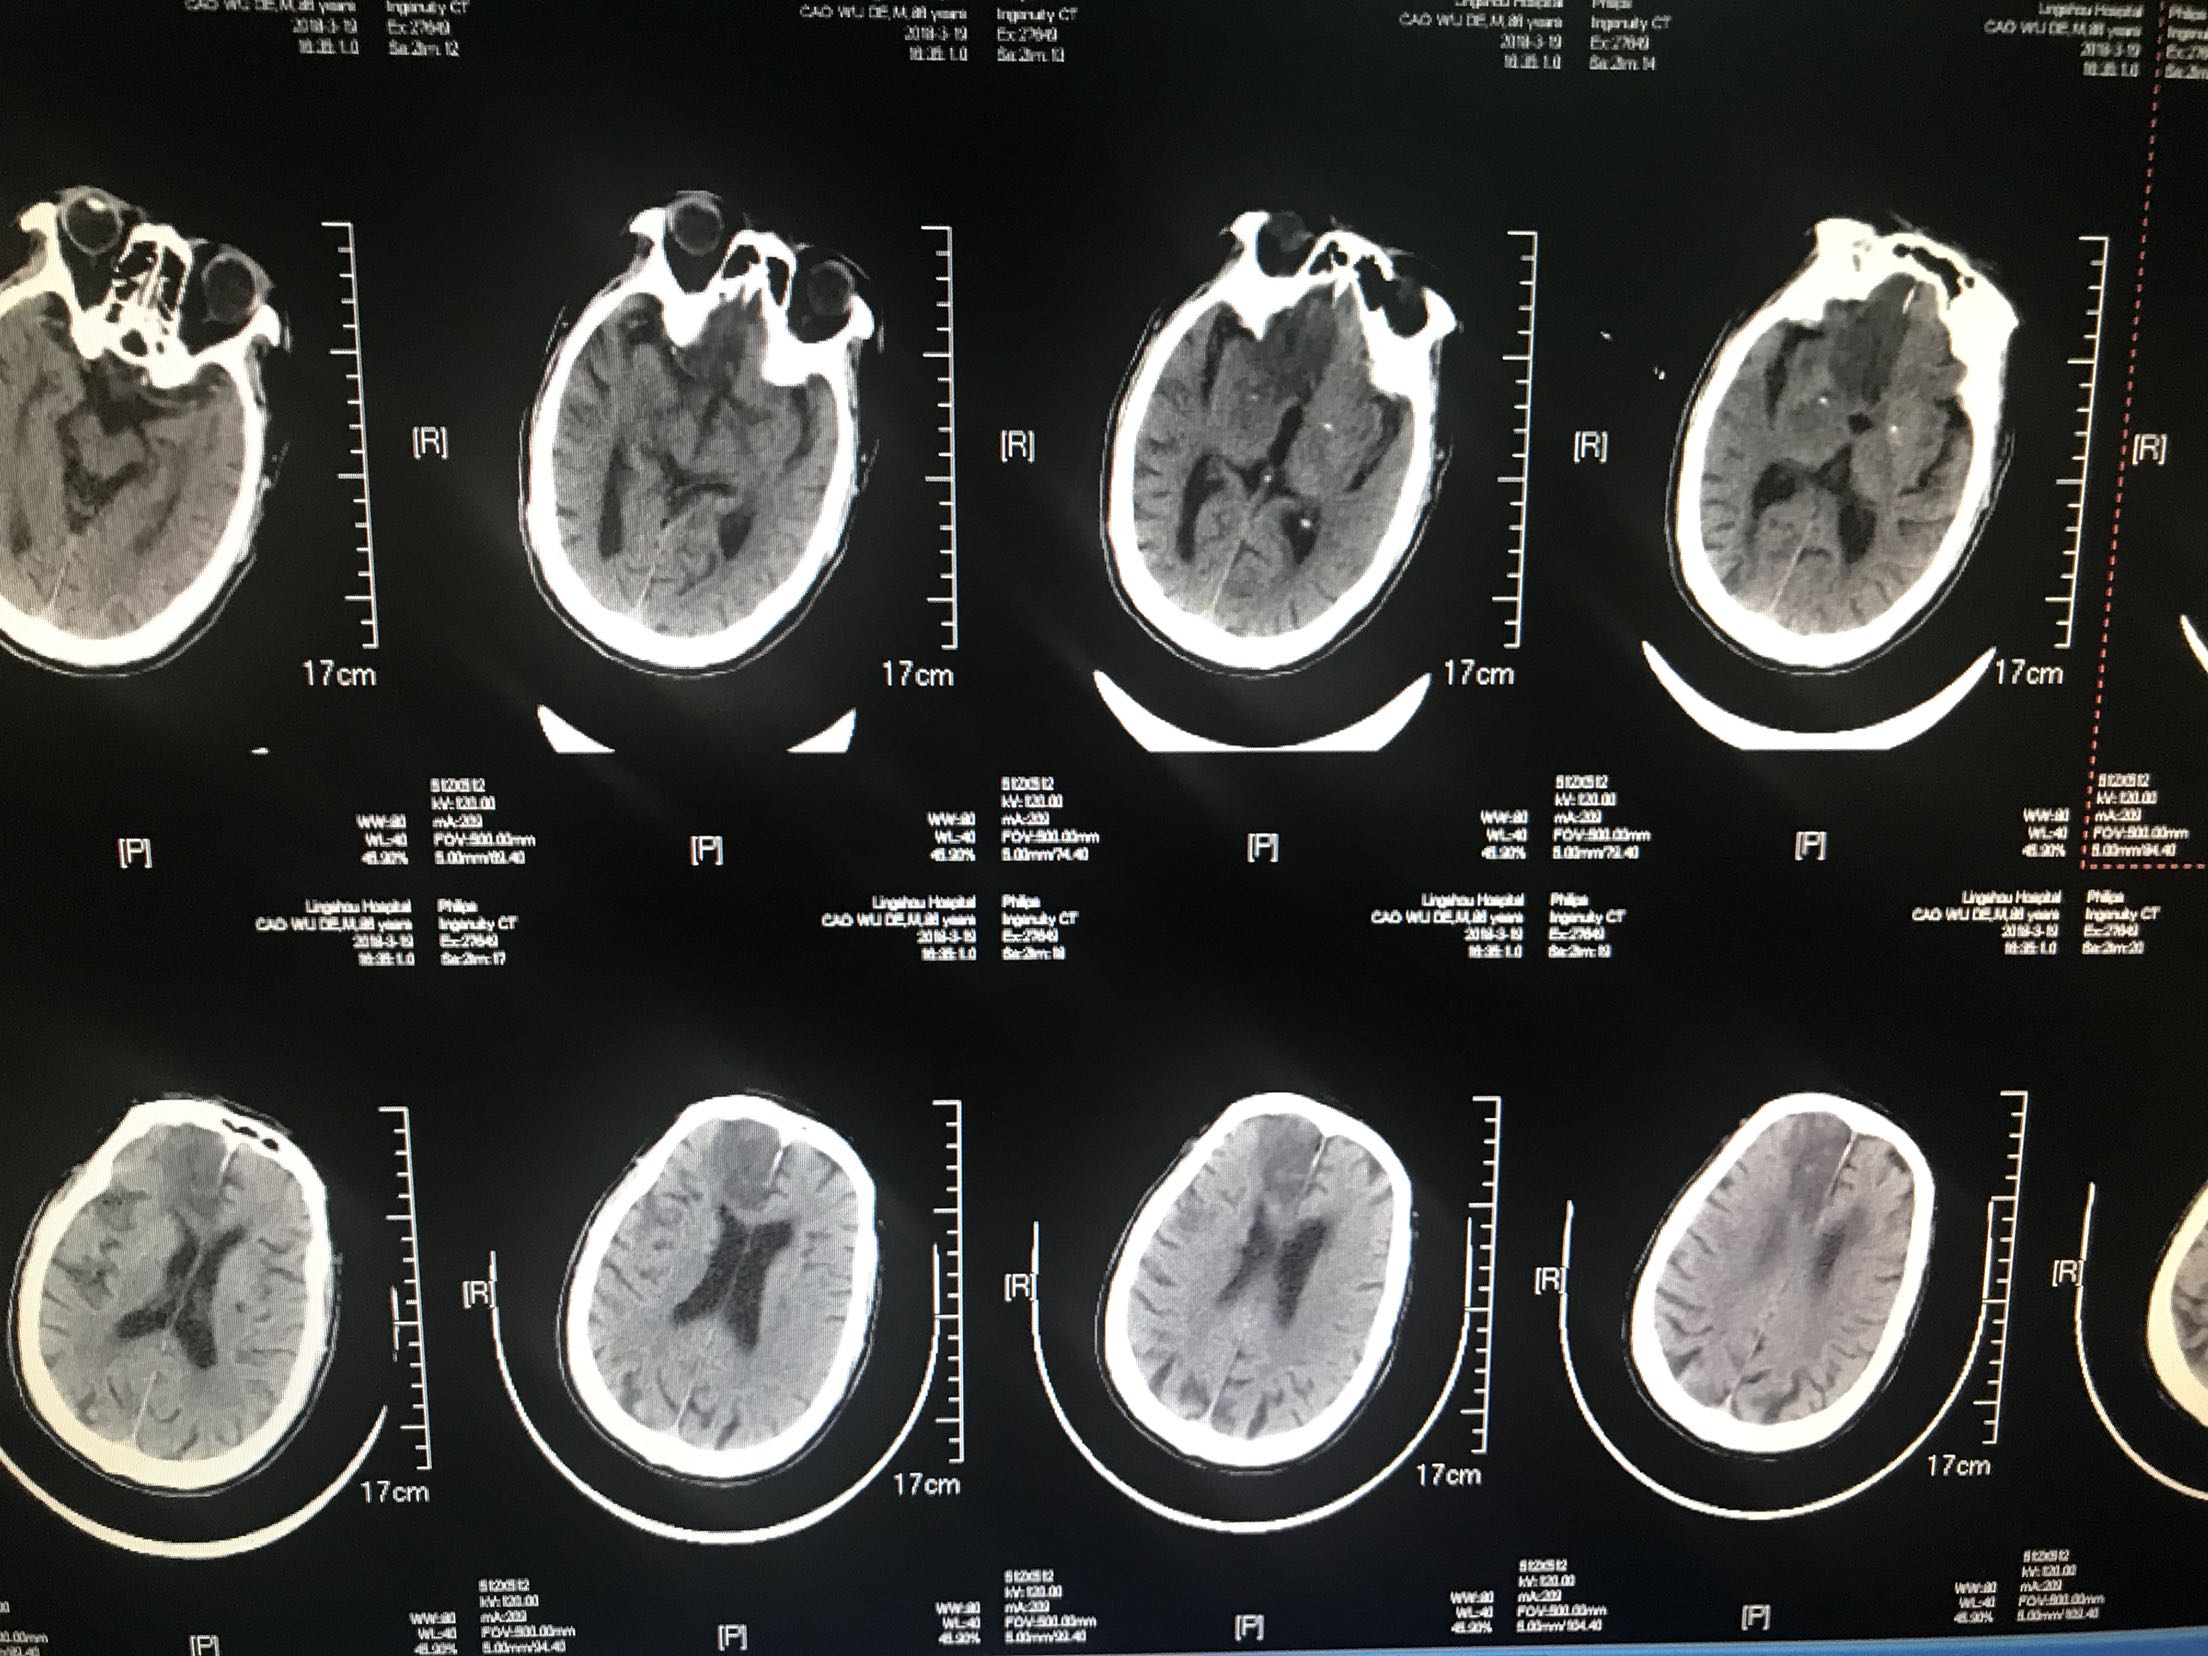

高龄大面积脑梗死

患者88岁不能行走1小时入院,房颤心衰起搏器安装痴呆病史,患者1小时前被家人发现倒在地上,不能言语,不能行走,急诊查血压210/120mmhg,查透头颅Ct够收住院

诊断 处理

脑梗死,房颤,高血压,给于曲克芦丁脑蛋白水解物,阿司匹林,阿托伐他汀,丁苯酞,醒脑静,马来酸氨氯地平,氨溴索等治疗